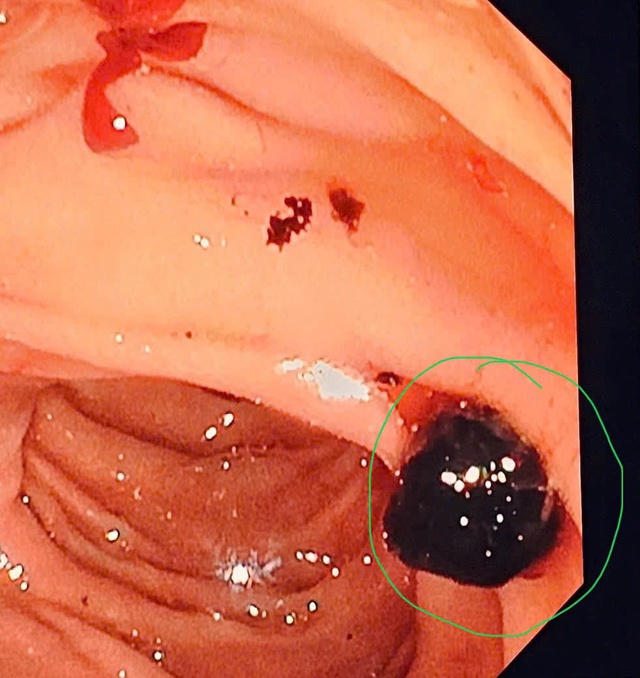

Hình ảnh viên sỏi trên màn hình nội soi.

Mới đây, Bệnh viện Đa khoa tỉnh Thanh Hóa tiếp nhận người đàn ông 72 tuổi, trong tình trạng đau bụng vùng thượng vị và hạ sườn phải, đau âm ỉ liên tục tăng dần, ăn uống khó tiêu, mệt mỏi. Qua thăm khám và làm các xét nghiệm cận lâm sàng, bệnh nhân được chẩn đoán tắc ống mật do sỏi mật. Hình ảnh nội soi cho thấy có hai viên sỏi đường mật với kích thước lần lượt khoảng 6mm và 7mm. Bệnh nhân được tiến hành nội soi mật tụy ngược dòng can thiệp (ERCP) để lấy sỏi, giải phóng tắc nghẽn đường mật. Sau can thiệp, sỏi được lấy ra thành công, đường mật lưu thông tốt, bệnh nhân hết đau, ăn uống trở lại bình thường và được ra viện trong tình trạng ổn định.